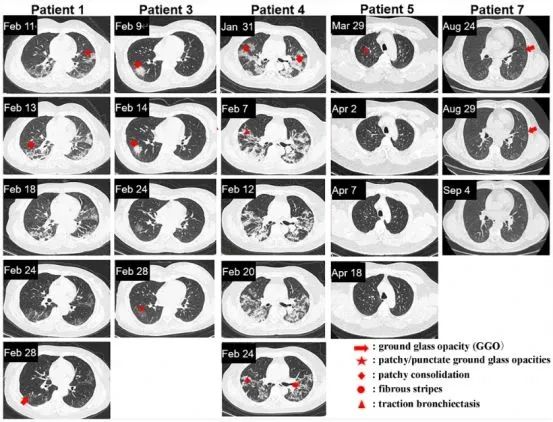

其他五名患者的 CT 圖像如下圖所示,能發(fā)現(xiàn)從一開始就接受外泌體治療的人(患者 5、7)和抗病毒治療一段時間后再接受外泌體治療的人(患者 1、3、4)在肺部病變完全吸收的時間之間存在顯著差異。

注:患者 1、3、4、5 和 7 的胸部 CT 圖像